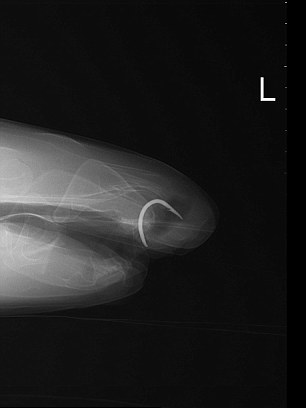

Βέβαια, δεν ήταν πάντα έτσι! Ξεκίνησε ως «κρεατοφάγος, αλλά μετά από μια επέμβαση στην οποία υποβλήθηκε το 2009 για να της αφαιρεθεί ένα σκουριασμένο αγκίστρι από το σαγόνι της… άλλαξε διατροφικές συνήθειες!